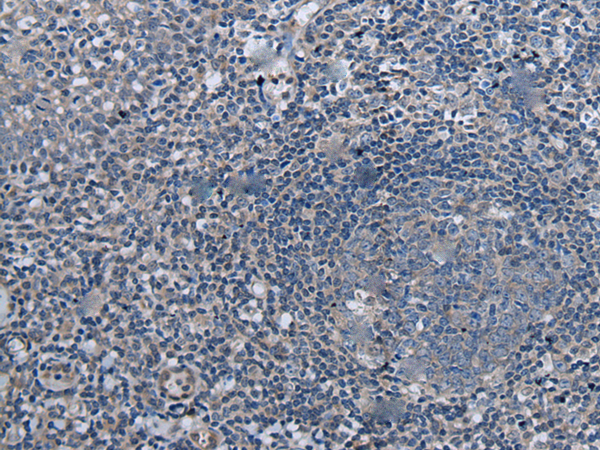

IHC positive control:

Human colorectal cancer and human tonsil

IHC Recommend dilution:

40-200